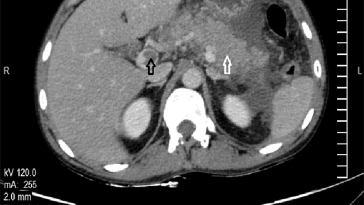

Understanding Portal Vein Aneurysm and Extrahepatic Portal Obstruction The story of portal vein aneurysm (PVA) intertwined with extrahepatic portal obstruction (EHO) is both a fascinating and cautionary tale in modern medicine. When we look at these conditions, we see not only their existence as rare vascular events but also a journey that involves tricky parts […] More